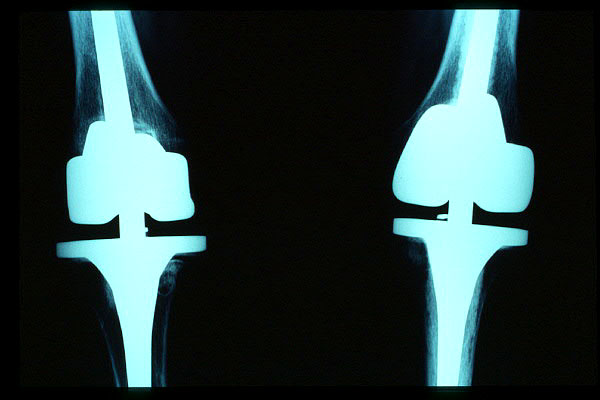

Prótesis completa de rodilla. Frontal.

Prótesis completa bilateral de rodillas.